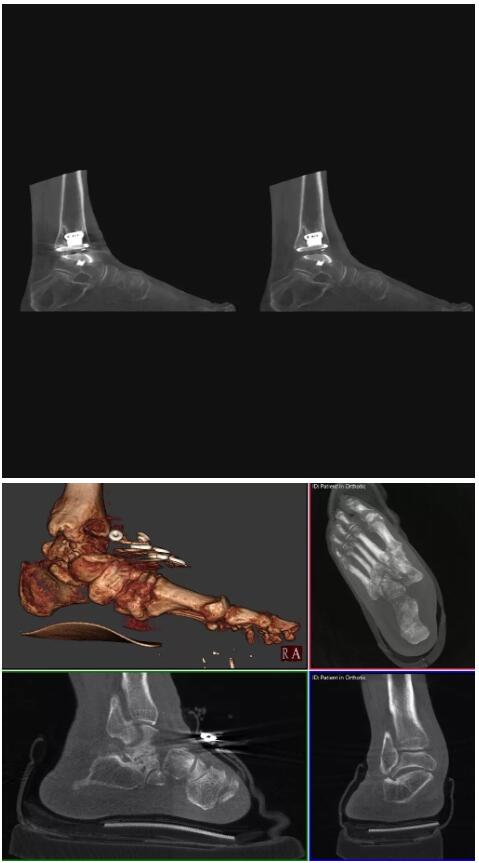

比如上面這款專用于足部和踝部掃查的CT成像系統(tǒng),患者在進(jìn)行CT掃查時(shí)只需要站在上面即可,雙腳站或者單腳站都可以,當(dāng)然,如果患者不是那么方便站著做完CT掃查,也可坐在上面。

這款CT掃查系統(tǒng)自帶屏蔽裝置,它的體積非常小,僅需要極小的空間即可,并不像常規(guī)CT那樣需要一間單獨(dú)的檢查室。此外,這種CT掃查的速度非常快,僅需30秒左右可以完成檢查,輻射劑量相對(duì)常規(guī)的CT要少許多,尤其適合醫(yī)院的骨科使用。

而患者站著做足部或者踝部做CT檢查還有個(gè)好處是,可以檢查患者在負(fù)重的情況下,骨關(guān)節(jié)的真實(shí)情況,而躺著做CT掃查時(shí)未必能看出來。負(fù)重CT掃查特別是對(duì)于受傷的運(yùn)動(dòng)員或者舞蹈員來說意義更大,能夠更準(zhǔn)確地評(píng)估傷情,幫助他們盡早復(fù)原。

以下是這些“特立獨(dú)行”的CT所拍出來的圖像: